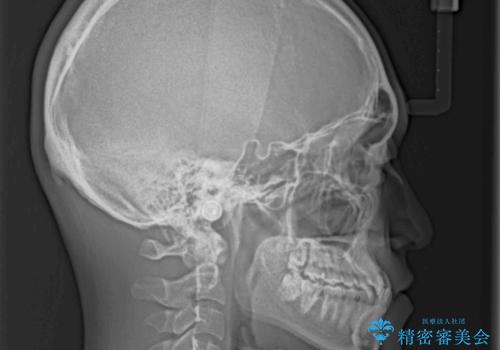

- 前歯のクロスバイトを気にして来院された患者様です。

歯がすり減って不揃いの形態となっていますが、まずは矯正治療によりクロスバイトを改善することとしました。